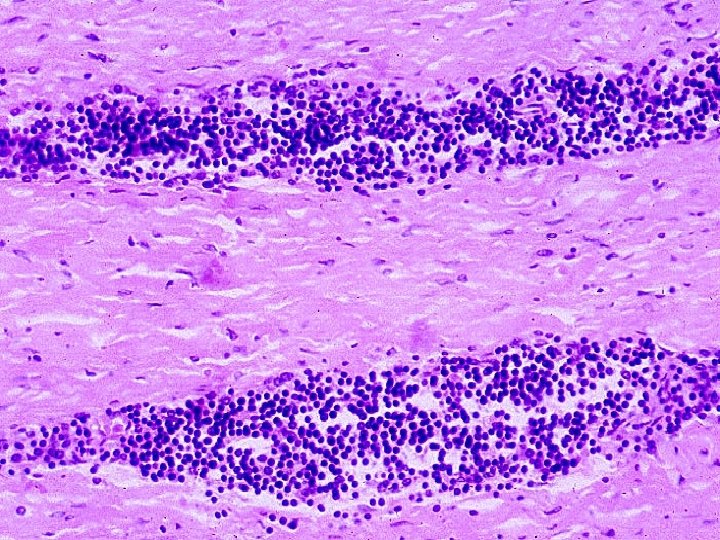

HISTOLOGICAL CHARACTERISTICS Infiltration with mononuclear cells (eg. macrophages, lymphocytes and plasma cells) due to persistent reaction to injury Tissue destruction induced by persistent agent or inflammatory cells Attempts at healing by connective tissue replacement of damaged tissue with angiogenesis and fibrosis

CHRONIC NON-SPECIFIC (NONGRANULOMATOUS) INFLAMMATION It is the continuation of a partially successful acute inflammation & reaction to persistent extracellular bacteria Histologically characterized by structureless unorganized diffuse infiltration of tissues by PMN’s and mononuclear cells